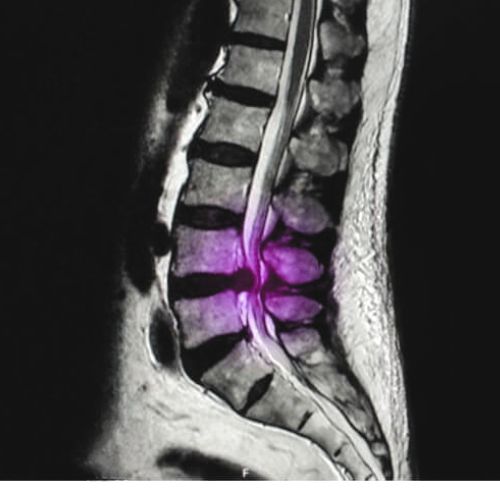

Hernia Discal Lumbar

Desplazamiento del material del disco intervertebral en la zona lumbar, que comprime raíces nerviosas. Produce dolor lumbar, ciática, hormigueo, debilidad y limitación funcional en las extremidades inferiores.